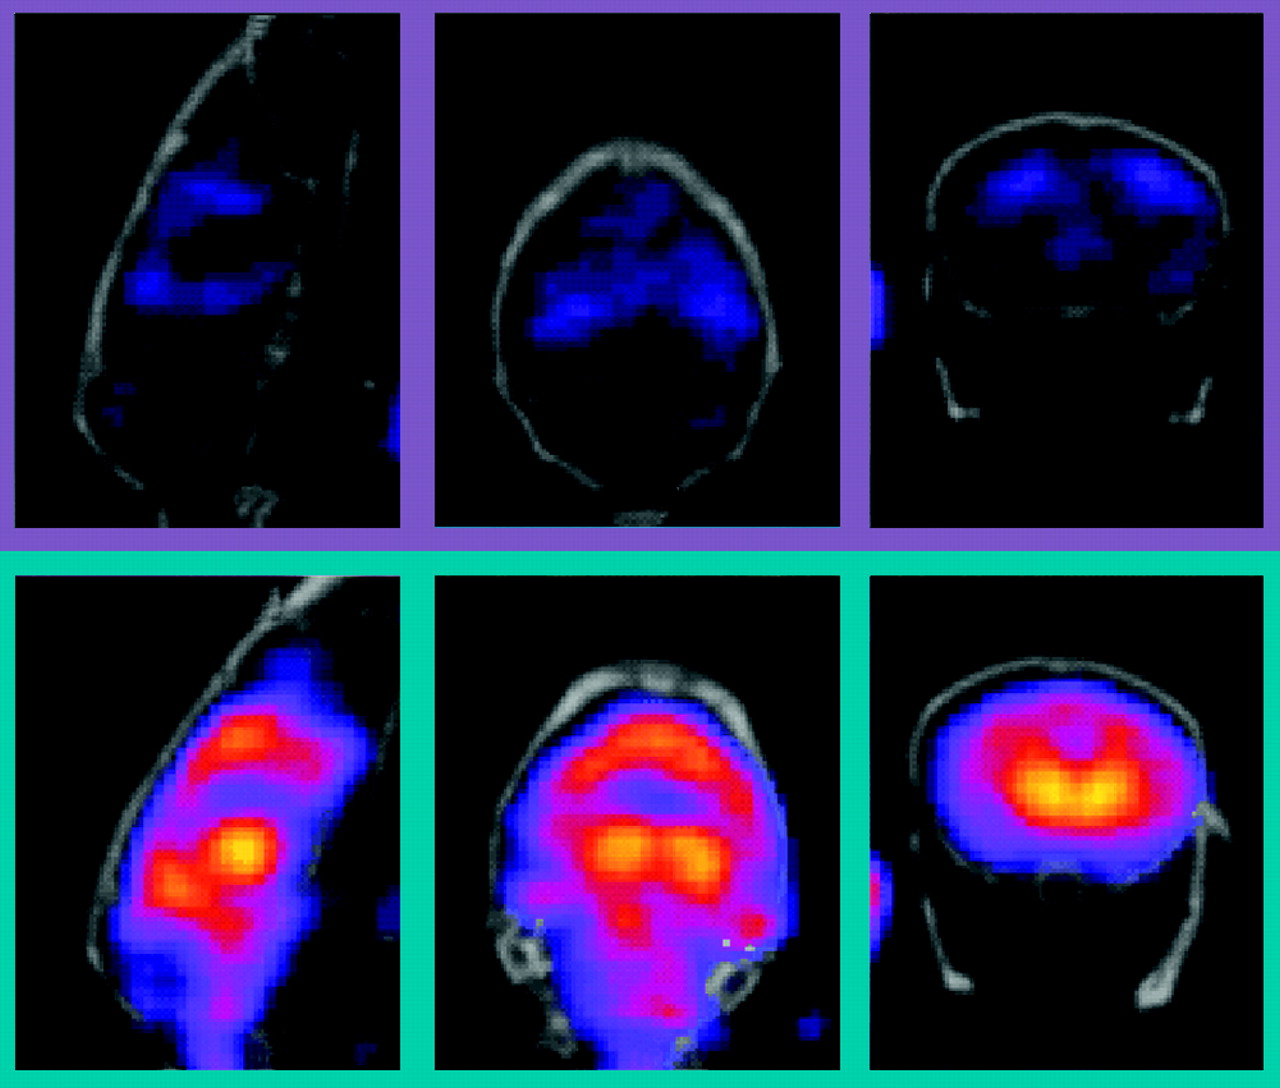

In vivo imaging of the neuronal nicotinic receptor β2 subtype. Knock-out (KO) and wild-type (WT) mice were imaged using the [123I]5-IA SPECT tracer. Specificity of target engagement of the PET/SPCET tracer can be assessed using genetically modified mice. We examined the binding specificity of [123I]5-IA to neuronal nicotinic receptor subtypes in KO (n= 4) and WT (n=2) mice. Fifty minutes after the infusion of 0.5mCi tracer, each mouse was imaged for forty-five minutes. Representative images clearly show the reduction of tracer uptake in KO mice, and quantitative region-of-interest analysis indicated significant decreases in binding activity at both prefrontal cortex (PFC) and thalamus.